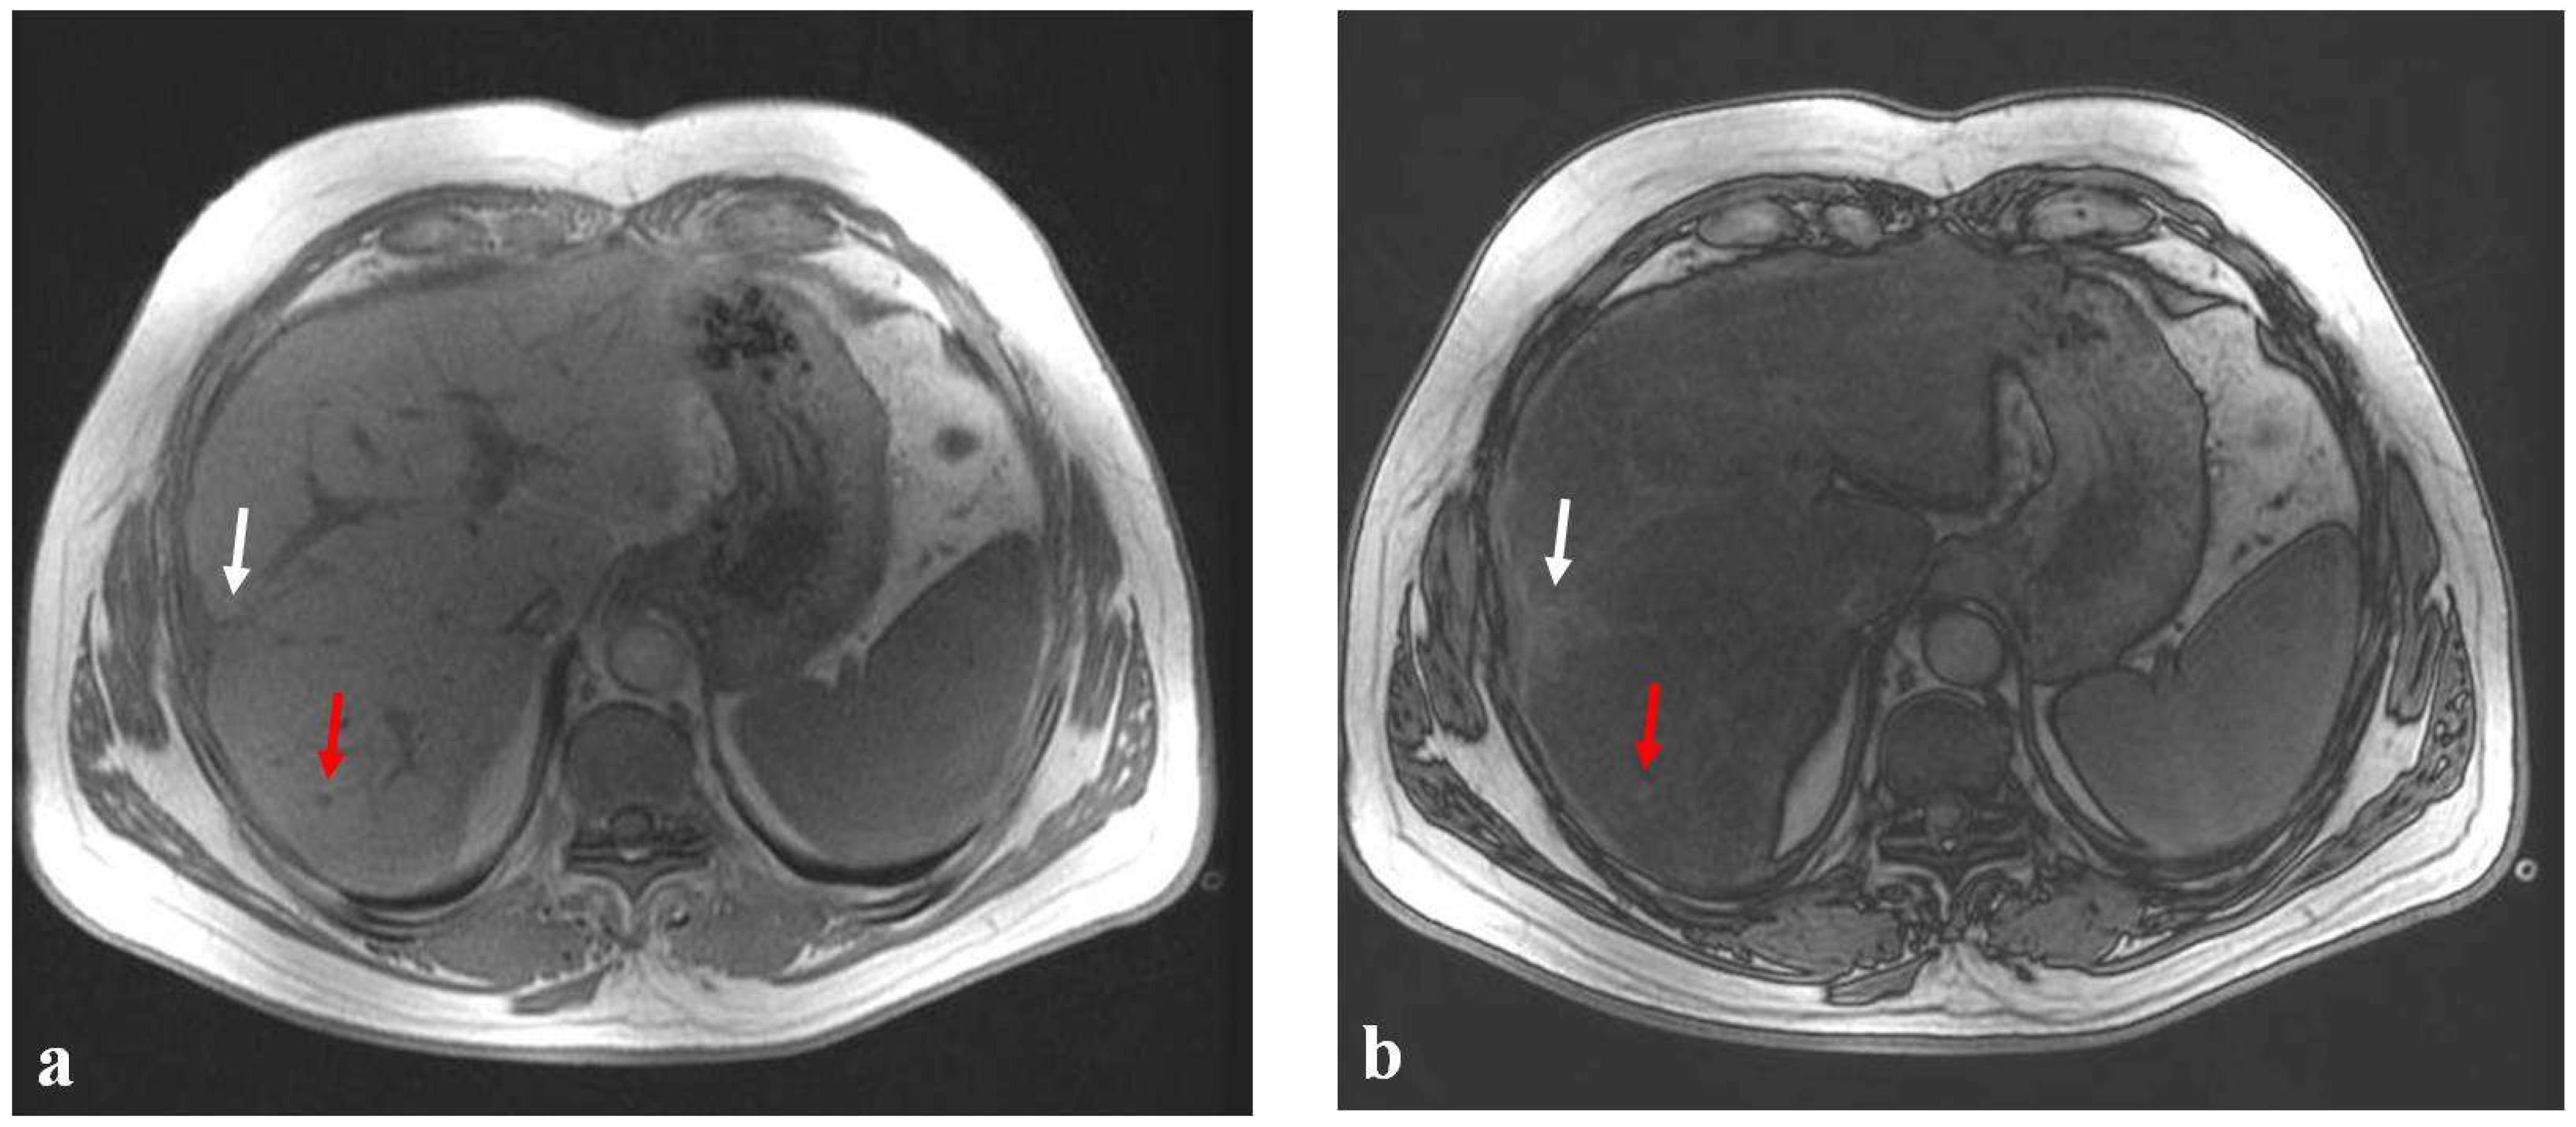

Figure 2.

(a–c) A 38-year-old man with liver metastases from rectal cancer undergoing neo-adjuvant chemotherapy with 5-fluoroacil and irinotecan (FOLFIRI). After chemotherapy, the axial T1-weighted in-phase image (a) showed diffuse hyperintensity of the liver with two poorly identifiable metastases, which had good therapeutic responses (white and red arrows), and the axial T1-weighted opposite-phase image (b) demonstrated a loss of signal at the level of the non-tumor-bearing liver parenchyma, suggesting hepatic steatosis. The MR imaging proton-density fat fraction (PDFF) map (c) showed the percentage of fat calculated from ROIs placed in the two hepatic lobes (right, 26% and left, 21%), in the subcutaneous fat (94%), and in the muscle (3%).